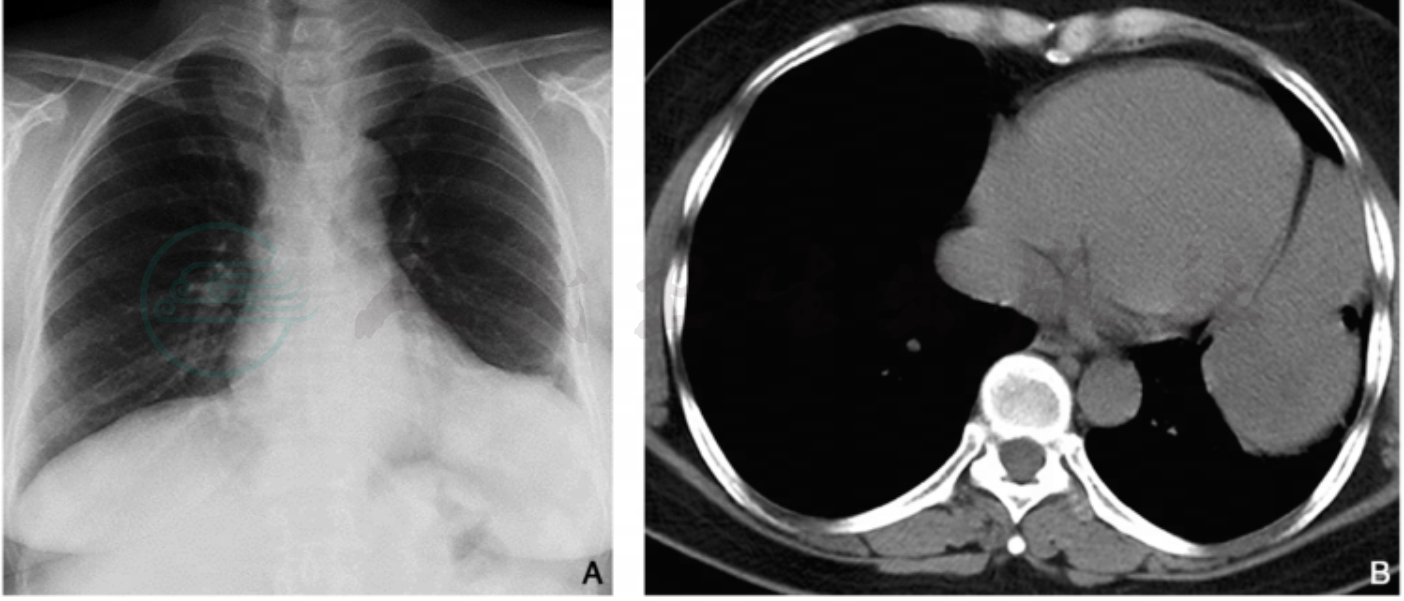

图1 膈肌肉瘤

注:女性,54岁,胸部X线片(A)示左侧膈肌局限性升高,左肋膈角变浅;CT平扫横断面图像(B)示左侧胸腔下部不规则软组织肿块,密度尚均匀;CT增强横断面(C)及冠状位(D)图像可见肿块不均匀强化,冠状位清晰显示肿块与膈肌广基底相连,沿膈肌生长充满左侧肋膈角。